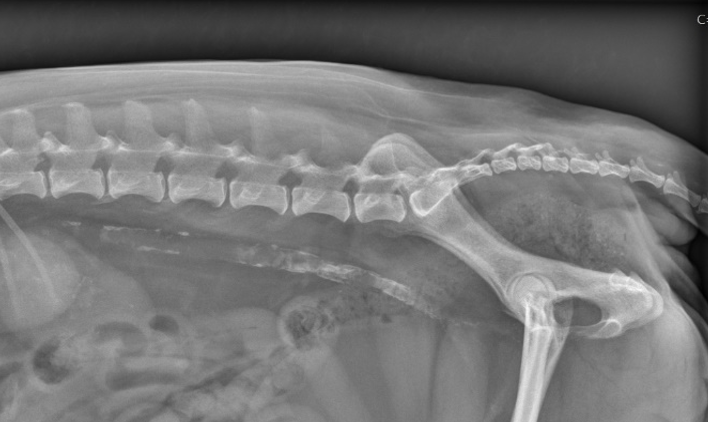

40

Which radiograph is normal vs. abnormal? Why?

Top: abnormal; generalized osteopenia; relative increase in opacity of vertebral endplates Bottom: normal